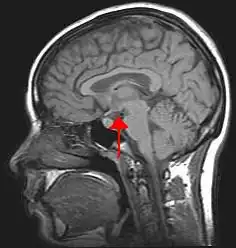

Der Hypothalamus (von altgriechisch ὑπό hypo „unter“ und θάλαμος thálamos „Zimmer, Kammer“) ist ein Teil des Gehirns und befindet sich direkt über der Hypophyse. Der Hypothalamus ist ein Abschnitt des Zwischenhirns (Diencephalon) im Bereich der Sehnervenkreuzung (Chiasma opticum). Medial wird der Hypothalamus vom dritten Ventrikel, kranial vom Thalamus begrenzt. Das Infundibulum, der sogenannte Hypophysenstiel, verbindet den Hypothalamus mit der Hypophyse, deren Hinterlappen noch als Teil des Hypothalamus bezeichnet wird.